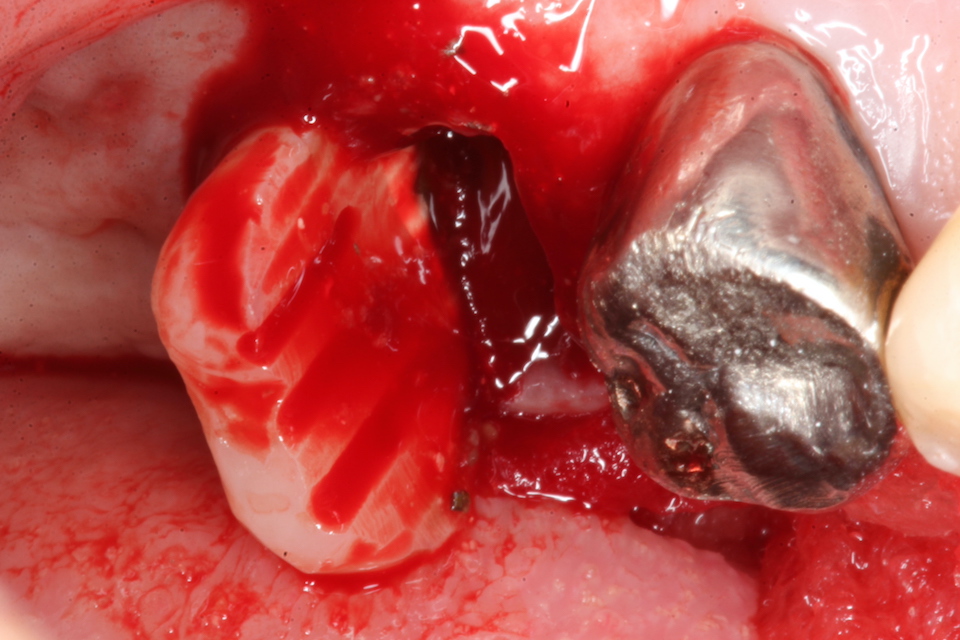

今日の抜歯再植術シリーズ39.1 2025.11.14

今日の抜歯再植術シリーズ39.0 2025.11.13

今日の抜歯再植術シリーズ38.3 2025.10.14